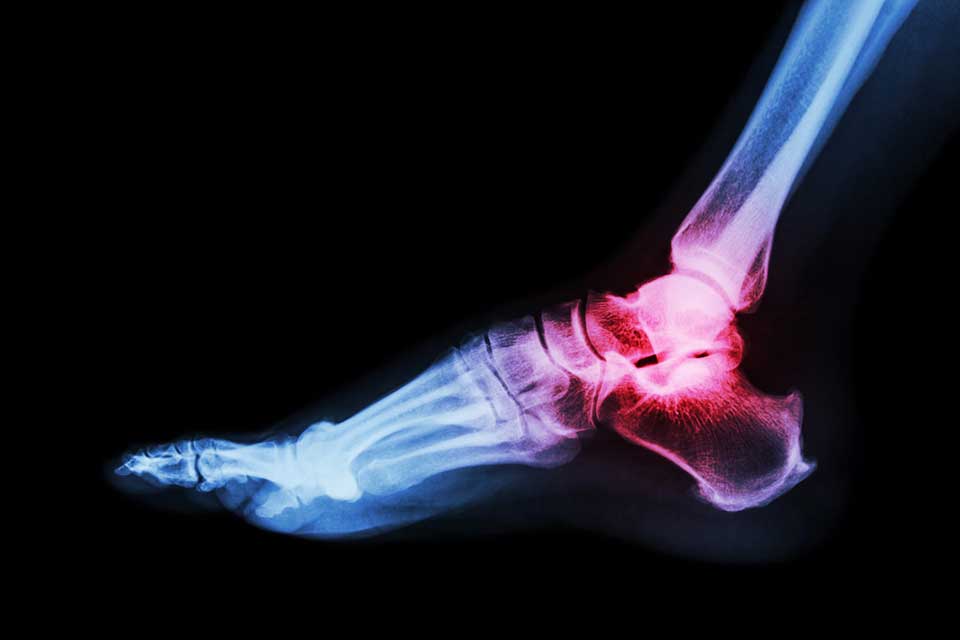

Gout is a common form of inflammatory arthritis, which affects 2.4% of adults in the UK. The painful condition is caused by high levels of uric acid in the blood which develops needle-like crystals in the joint.

The research found that the number of patients with fractures also suffering with gout, was similar to those without the condition. In addition, it found that the medication used to lower the uric acid levels in gout patients had no effect on the long-term risk of fractures.